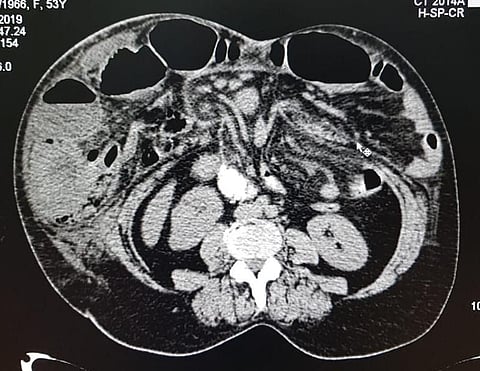

وفي التفاصيل، أنه بعد إجراء الفحوص الطبية اللازمة للمريضة تبيّن وجود فتق كبير بالأمعاء سبّب لها انسداداً معوياً؛ ما استدعى القيام بتدخل جراحي سريع.

وأجريت للمريضة عملية فتح لمنطقة البطن لإصلاح جدار البطن ومن ثم وضع شبكة برولين لتدعيم منطقة الفتق، وبحمد الله تماثلت المريضة للشفاء، وهي بصحة جيدة.